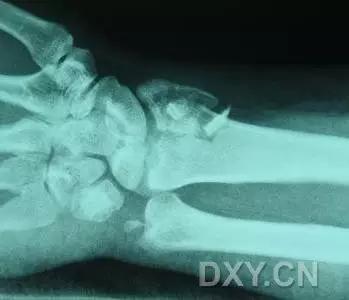

1. Barton 骨折

桡骨远端有移位的、不稳定的且经关节的桡骨远端骨折。可向掌侧也可向背侧移位。

(来源:radiology assistant)